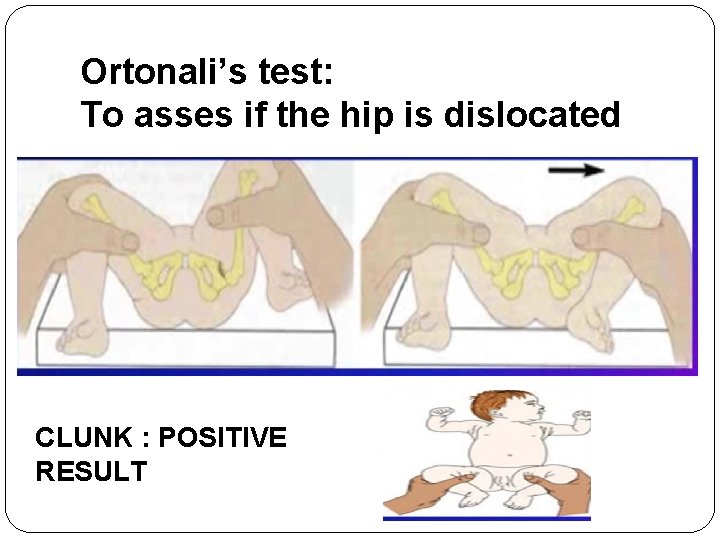

HOW TO ASSES HIP STABILITY IN INFANTS: � 1. Barlow test : a maneuver that is performed by adducting the hip while applying light pressure on the knee, directing the force posteriorly. If the hip dislocates (pops out of socket with a „clunk‟ is felt), the test is considered positive. The test is harmful and shouldn’t be done. � 2. Ortolani test : relocates the dislocation of the hip joint that has just been elicited by the Barlow maneuver by abducting the hip joint. � Barlow and Ortolani tests are inapplicable after 3 months of age because of certain changes that happen in the hip joint and make it fixed and no more reducible by that age. Specifically, this tests for posterior dislocation of the hip.

Ortonali’s test: To asses if the hip is dislocated CLUNK : POSITIVE RESULT